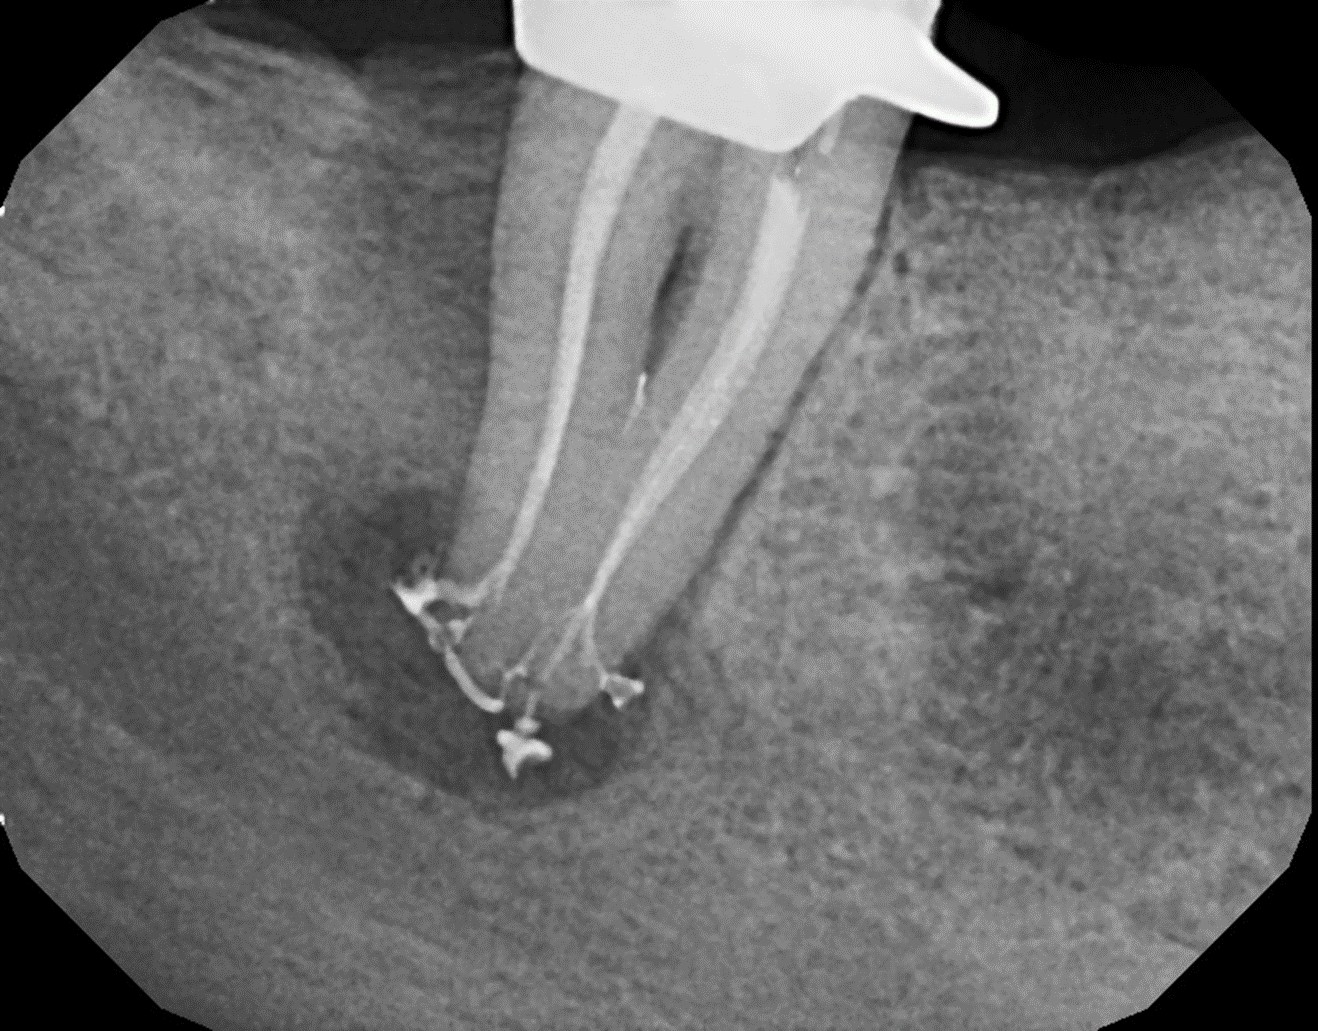

With this technology, gentle vortical flow is induced within the root canal system with a slight negative pressure at the apices, which reduces the potential for extrusion. The result is a more complete removal of pulp tissue, bacteria, and bacterial biofilm within the root canal, including debris in anatomically complex structures (eg, isthmi, lateral canals, multiple apical foramina).18-20 In other words, it can clean and disinfect even where a file or rotary instrument cannot reach (Figure 15 through Figure 18). All this is accomplished with minimal instrumentation, most of the time to a size as small as a .04 taper #15 or #20 rotary instrument. In addition, conservation of root dentin results in a stronger root, which may increase the survival rate of the treated tooth.7

Fig 15. Postoperative obturation radiographs after multisonic ultracleaning technology, revealing complex and intricate canal anatomy.

Figure 15